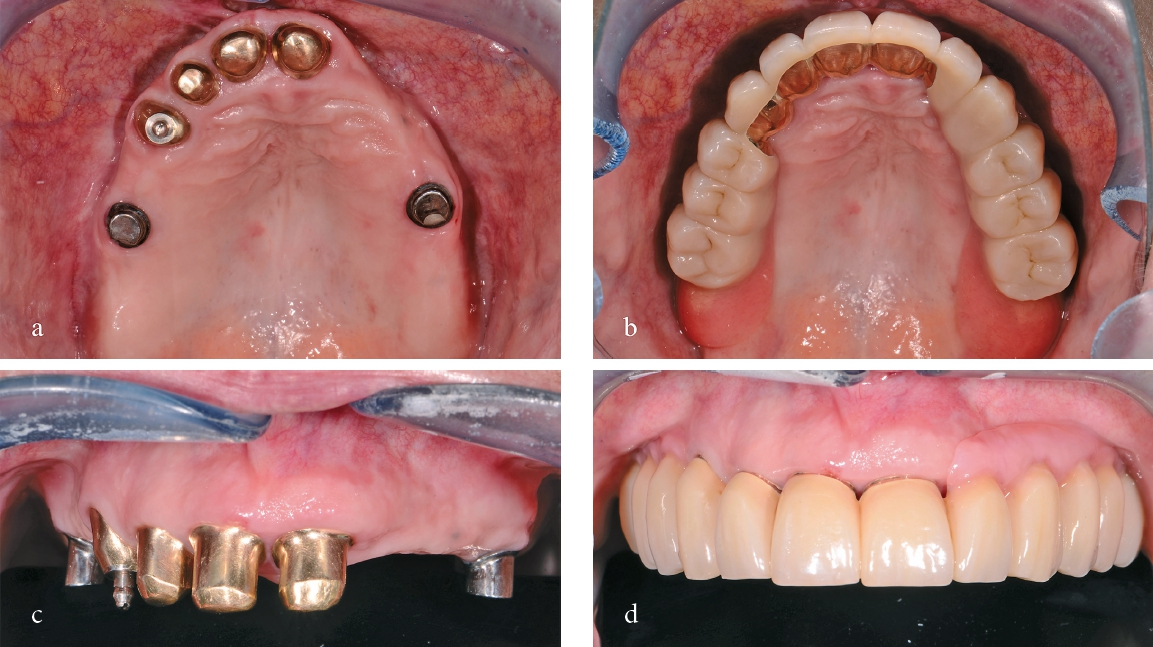

In einem nächsten Schritt wurden die Primärteile provisorisch fixiert und zusammen mit den Implantaten und den Schleimhautarealen überabgeformt (ImpregumTM, 3M) zur Herstellung des Meistermodells (Abb. 15). Die Position der Implantate wurde mittels „Verification Stent“ rückkontrolliert und die vertikale und horizontale Kieferrelation intraoral mittels Handbissnahme verschlüsselt. Aufgrund der nicht unerheblichen Achsendivergenz zwischen den Implantaten und den natürlichen Pfeilerzähnen wurde entschieden, die Implantate anstelle von konfektionierten Einzelelementen mit individuellen CAD/CAM-Teleskopkronen (Atlantis Abutments, Dentsply Sirona, Wals bei Salzburg, Österreich) zu versorgen. Konfektionierte Einzelelemente wären durch die Achsendivergenz einem erhöhten Verschleiß unterzogen gewesen, was wiederum mit einem gesteigerten Nachsorgebedarf verbunden gewesen wäre. Nach mehreren Set-up-Einproben konnte schließlich auch das Sekundärgerüst hergestellt werden. Sämtliche Sekundärteile wurden dabei als Vollgussteile designt und mit dem Modellgussgerüst verklebt, mit Ausnahme der Sekundärteile für die Implantatteleskopkronen, welche zur Sicherstellung der Passivität intraoral verklebt werden sollten (Abb. 16 u. 17). Sowohl Primär- als auch Sekundärteile wurden für eine höhere Härte während 30 min bei 400°C vergütet. Anschließend konnte das geschlüsselte Set-up und auf das Gerüst aufgepasst werden. Um die Pfeilerzähne wurde die Prothese offen gestaltet, um eine natürliche Umspülung der Pfeilerzähne zu ermöglichen. Auf ein Palatinalband konnte aufgrund der guten Kammverhältnisse und des breiten Unterstützungspolygons verzichtet werden. Nach einer letzten klinischen Einprobe konnte die Prothese durch den Zahntechniker individualisiert und fertiggestellt werden (Abb. 18).

Die Teleskopkronen und die Wurzelstiftkappe wurden mit Glasionomerzement (KetacTM Cem, 3M) sukzessive einzeln eingesetzt. Die Implantatteleskopkronen wurden mit einem Anzugsdrehmoment von 35 Ncm festgeschraubt und mit weißer Guttapercha und Glasionomerzement (KetacTM Bond, 3M) verschlossen. Nach einer Tragedauer von einer Woche, in der sich die Prothese einlagern konnte, wurden die Sekundärteile der Implantatteleskopkronen und die Matrize der Wurzelstiftkappe intraoral verklebt (Super-T, American Consolidated Manufacturing, Conshohocken, USA) (Abb. 19).

Definitive Versorgung im Unterkiefer

Sechs Monate nach Fertigstellung der Oberkieferhybridprothese folgte die definitive Versorgung im Unterkiefer. Die verblockten und nicht passgenauen Kronen 34-35i-36i wurden entfernt und ein direktes Provisorium für den Zahn 34 angefertigt. Die beiden Implantate 35i und 36i wurden mit standardisierten Healing-Abutments provisorisch versorgt. Nach chirurgischer Weichteilkorrektur und Nachpräparation des Pfeilerzahnes 34 wurde die Situation abgeformt und mit neuen einzelnen VMK-Kronen und -Implantatkronen versorgt (Abb. 20 u. 21).